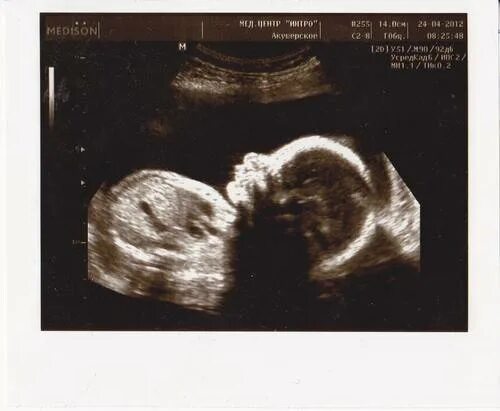

Узи 22 недели